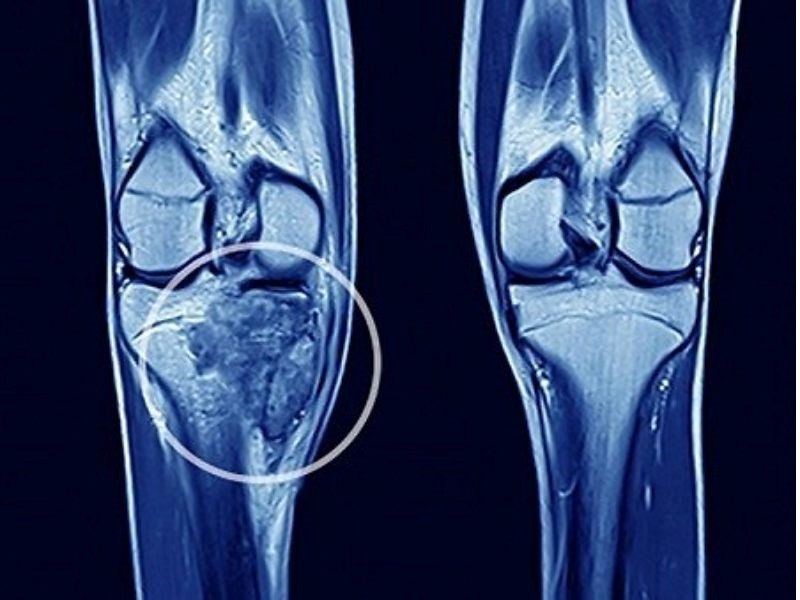

Chụp cộng hưởng từ

Kết quả chụp MRI cho phép bác sĩ quan sát rõ ràng hình ảnh xâm lấn tủy sống, các mô mềm xung quanh và ống sống. Đây là một kỹ thuật chẩn đoán có độ nhạy cao, giúp đánh giá chính xác tình trạng của tủy xương và phát hiện những thay đổi bất thường.